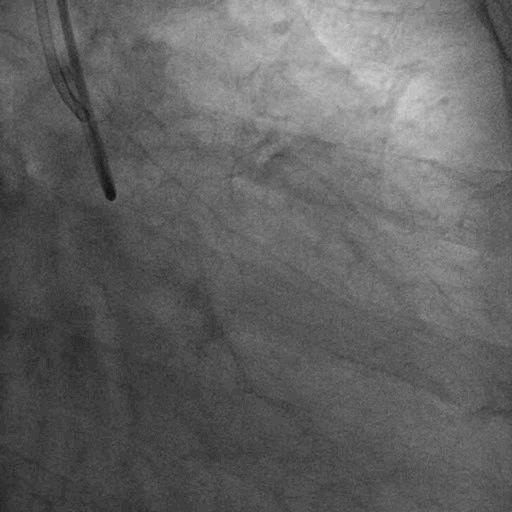

术前造影:

双侧造影: